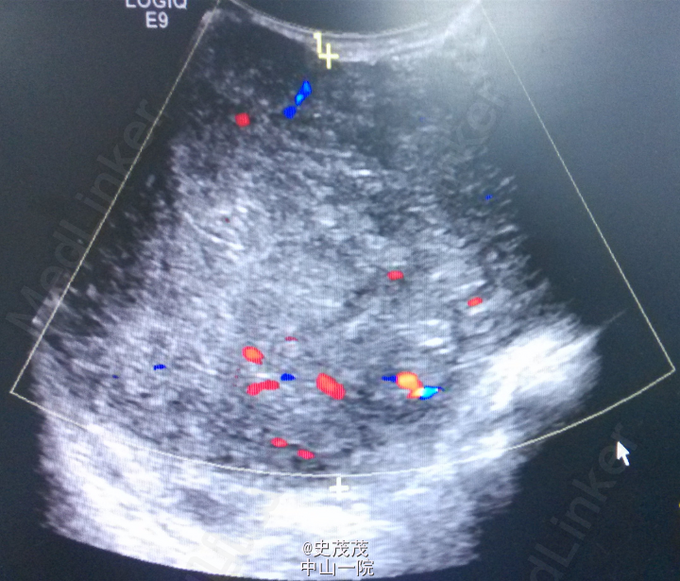

47岁,女性,因“发现右乳肿物2年余”入院。患者于2年前无明显诱因发现右乳肿物,局部哟红肿、疼痛不适,乳头无异常溢血溢液,肿物于月经来潮前疼痛加剧。半年来肿物逐渐增大,伴疼痛。既往史:2年前因“右侧乳房巨大乳腺纤维瘤”行纤维瘤切除术。查体:双侧乳房对称,皮肤未见桔皮征及酒窝征,乳头无凹陷、畸形。右乳外上象限可及一约20cm×10cm大小肿物,质中,表面光滑,边界清,活动度可,无压痛,与皮肤无黏连。挤压乳头无溢血、溢液。同侧腋窝及锁骨淋巴结均未及明显异常。对侧乳房未及异常。辅助检查:乳腺B超:1、右侧乳房局灶性病变,位于全乳腺体层,范围210×100mm,呈低混合回声,境界清晰,呈膨胀式生长。彩色血流检查瘤体内部见丰富血流信号,考虑叶状囊肉瘤,符BI-RADS 5 级;2、符合乳房囊性增生病超声改变。诊断:右侧乳房肿物:叶状囊肉瘤?治疗方法:行“右乳肿物切除术”,术中在外上象限切出肿瘤大小约20×20cm大小,浸润皮肤及胸大肌,实性,术中冰冻为叶状囊肉瘤,因需待石蜡结果,延缓手术。术后石蜡病理:病变符合乳腺交界性叶状肿瘤伴导管上皮非典型性。予密切随诊。应患者要求,择期行二期重建。总结:见下图乳腺癌NCCN指南2015年V2版叶状肿瘤。